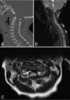

Stenosis of cervical spinal canal

Spinal stenosis is an abnormal narrowing of the spinal canal or neural foramen that results in pressure on the spinal cord or nerve roots. Symptoms may include pain, numbness, or weakness in the arms or legs. [Source: Wikipedia ]